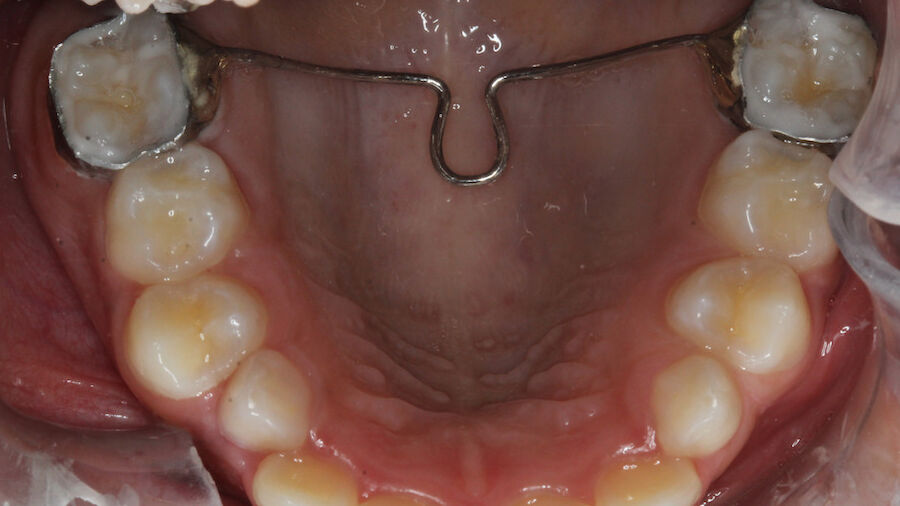

Arco transpalatino O Arco Transpalatino removível pode ser uma excelente alternativa para manter o espaço em pacientes na dentição mista. Para os profissionais que tem